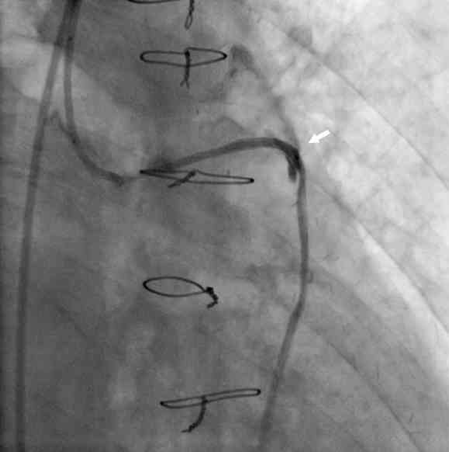

Figure 2. A stent graft was deployed to the perforation site, and the extravasation was successfully reduced (arrowhead) (click thumbnail to view larger image).

This aided in the successful sealing of the perforation (Figure 2) and stopping of the contrast leakage.

Although his vital signs were hemodynamically stable, the patient began to develop hemoptysis of fresh blood. Mild tachypnea was noted at the same time, and an oxygen mask (oxygen supply of 8 L/min) was applied without endotracheal intubation. His oxygen saturation was kept higher than 90% under the use of oxygen. The ACT was measured as 480 s. The Firestar 3.0 × 30 mm balloon was inflated at a low pressure (4 atm) to stop the extravasation of blood. The echocardiography performed immediately after did not show any evidence of pericardial effusion. Prolonged balloon inflation failed to stop the extravasation of blood. Therefore, the guiding catheter was changed to 7 Fr JR 3.5, and a GraftMaster 3.0 × 16 mm stent (Abbott Vascular) was deployed to the perforated site by using a maximum pressure of 14 atm. The contrast leakage from the lesion site decreased, but it did not stop completely. Concurrent administration of protamine was used to correct the anticoagulation of heparin, with a final ACT level of 189 s.